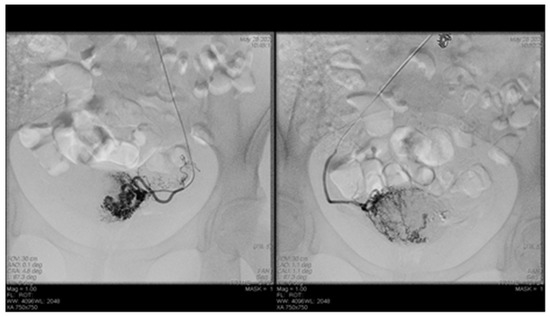

Endovascular procedures were used in 2.29% of cases with ectopic pregnancy (n = 26) (see Figure 4 and Figure 5), 1.23% of patients with arteriovenous malformation (n = 14) (see Figure 6), and 0.52% of patients with major hemorrhage of obstetrical causes (n = 6).

Figure 4. Pelvic artery embolization for cervical ectopic pregnancy.

Figure 5. Pelvic artery embolization for C-scar ectopic pregnancy.